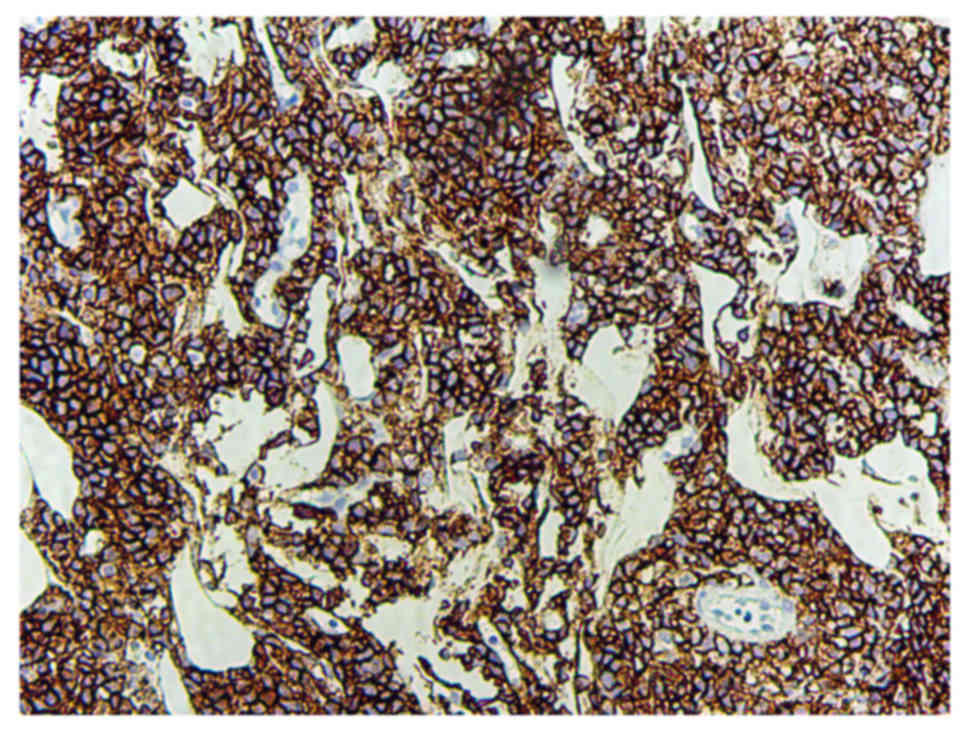

On admission, the following laboratory parameters were noted: Blood cell count 4.1×1012/l (normal range, 4.0–5.0×1012/l); dehydrogenase 181 U/l (normal range, 109–245 U/l); and cancer antigen-125; 29 kU/ml (normal range, 0–35.0 kU/ml). Baseline renal and liver function test results were also normal. Hepatitis B virus markers, hepatitis C virus antibody (Ab) and human immunodeficiency virus Ab tests were negative. Based on physical examination and laboratory findings, a surgical exploration was performed following a suspected diagnosis of cervical carcinoma or primary vaginal carcinoma. The mass was resected from the patient under anesthesia (Fig. 2). Immunohistochemistry and biopsy confirmed the lymphoid origin of the neoplasm (Fig. 3), and tumor cells were positive for cluster of differentiation 20 (CD20) (Fig. 4) and CD79a (Fig. 5). The bone marrow aspirate and biopsy did not reveal lymphomatous infiltration. A computed tomography (CT) scan of the chest and abdomen did not detect metastasis to other locations. The patient was diagnosed with stage IE primary vaginal large B-cell NHL disease based on the Ann Arbor system (5) for staging NHL. One month after the surgery, oncologists reviewed the patient and recommended 6 cycles of the CHOP regime (1,000 mg cyclophosphamide on days 1 and 8, 50 mg doxorubicin on day 1, vincristine 2 mg on day 1 and 100 mg prednisone on days 1–5 for 21 days/cycle). Rituximab was not used in the chemotherapy regimen for financial reasons.

The differential diagnosis of vaginal NHL includes other hematopoietic lesions (including granulocytic sarcoma and Langerhan's cell histiocytosis), carcinoma, malignant mixed Mullerian tumor, epithelioid leiomyosarcoma and endometrial stromal tumors, including endometrial stromal sarcoma, melanoma and extraosseous Ewing's sarcoma/primitive neuroectodermal tumor (13). The pathological diagnosis of DLBCL is based on morphology and immunophenotyping. DLBCL is a heterogeneous group of tumors consisting of large, transformed B cells with prominent nucleoli, a basophilic cytoplasm, a diffuse growth pattern and a high proliferation fraction. Tumor cells generally express pan-B cell antigens, including CD19, CD20, CD22 and CD79a (14). A screening panel consisting of CD45, CD3, CD20 and cytokeratin is useful in determining whether the tumor is a B-cell lymphoma (CD20+), T-cell lymphoma (CD3+), granulocytic sarcoma (only CD45+) or carcinoma (cytokeratin+) (9).